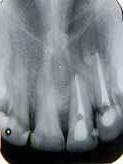

posteriorly on the left palate till the posterior vibrating line. There was no pointing of the lesion. IOPA and occlussal radiographs were taken (Fig1a & b). The IOPA revealed a huge radiolucent lesion with diffuse margins in relation to the periapical region of the upper left lateral which had a root canal filling and a separate smaller radioluscent periapically to the adjacent central incisor also. The occlussal radiograph showeda large radiolucent lesion on the palatal aspect in relation to the upper left lateral. It was decided to retreat the case and the patient was advised of the poor prognosis of the tooth.

Fig 1a: First visit (IOPA) Fig 1b: first visit (occlussal) Fig 2a: Pre obturation 14 months (IOPA) Fig 2b: Pre obturation 14 months (occlussal)

hypochlorite and hydrogen peroxide and then washed with saline. A closed dressing with calcium hydroxide was given and patient recalled after one month. Thereafter, periodic monthly appointments were given where the canal was irrigatedand closed irrigation with calcium hydroxide was given. After around 14 months after the first visit the swelling was completely absent and patient reported no pain. The periapical radioluscency was still present though localized to the periapical and reduced to around 5mm in diameter (Fig2a & b). This time the canals were obturated using lateral condensation technique (Fig 3). And the patient recalled after six months for a review. Six months after obturation it was seen that the periapical radioluscencywas almost absent with a mild crescent shaped radioluscent around the apex (Fig 4a & b). The patient had no symptoms to report. During the intervening six months the patient had crowns made to correct the discoloration. The patient was recalled after a period of six months to further review the healing.

One year after obturation the patient had absolutely no signs and no symptoms. The occlussal radiograph and periapical radiograph showed a very thin crescent shaped radioluscency at the apex (Fig 5).